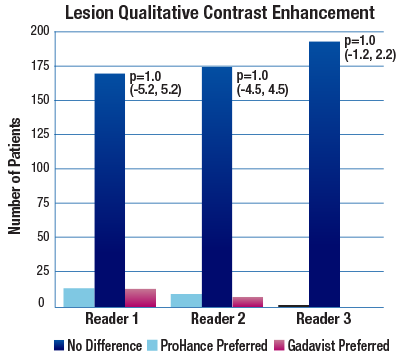

The TRUTH study results demonstrate no differences in contrast enhancement of lesion morphology.1

The 95% confidence intervals for all qualitative assessments confirm that ProHance is not inferior to Gadavist.1

No significant differences noted by any reader for any parameter:1

- Lesion Qualitative Contrast Enhancement